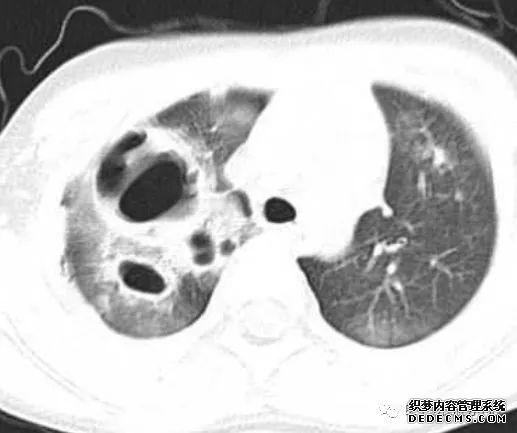

张力性纵隔气肿影像表现及严重度分级